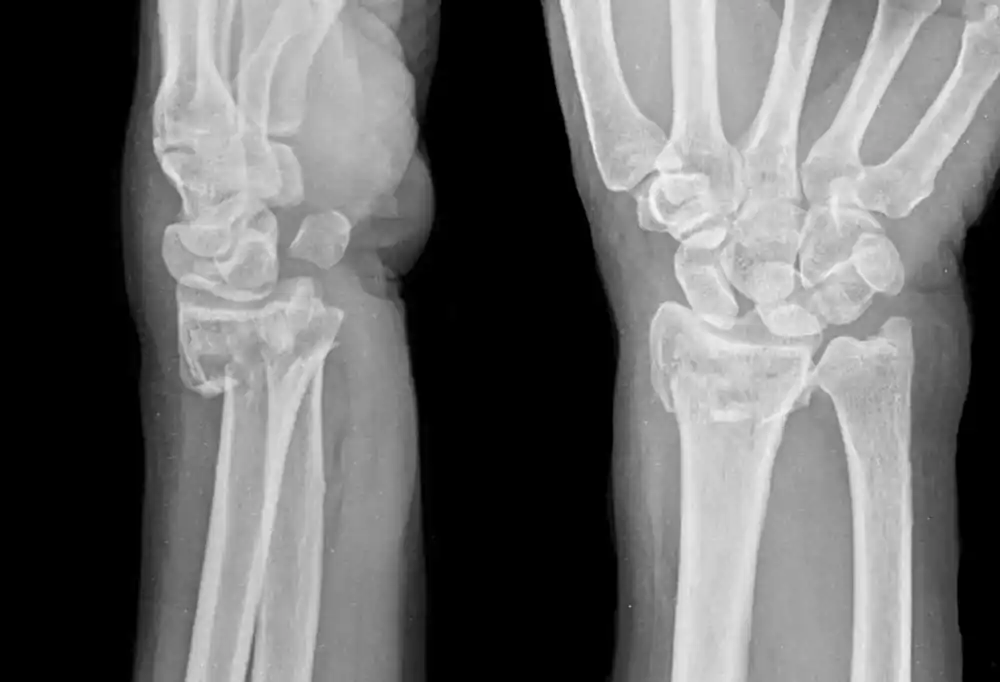

• Röntgen: Kemiğin kırık olup olmadığını net bir şekilde gösterir.

Distal radius kırığı, bileğin en yaygın kırıklarından biridir ve genellikle düşme gibi travmalar sonucu meydana gelir. Radius kemiği, kolun alt kısmındaki büyük kemiklerden biridir ve bileği destekler. Distal radius, bu kemiğin bileğe yakın olan kısmıdır. Bu kırık, yaşlı bireylerde daha yaygın olsa da, gençlerde de spor yaralanmaları veya kazalar sonucunda görülebilir.

Distal radius kırığı, ön kolun başparmak tarafındaki kemiği olan radiusun, bileğe yakın kısmında meydana gelen kırıklardır. Genellikle elin üzerine düşme sonucu oluşur ve oldukça yaygındır.